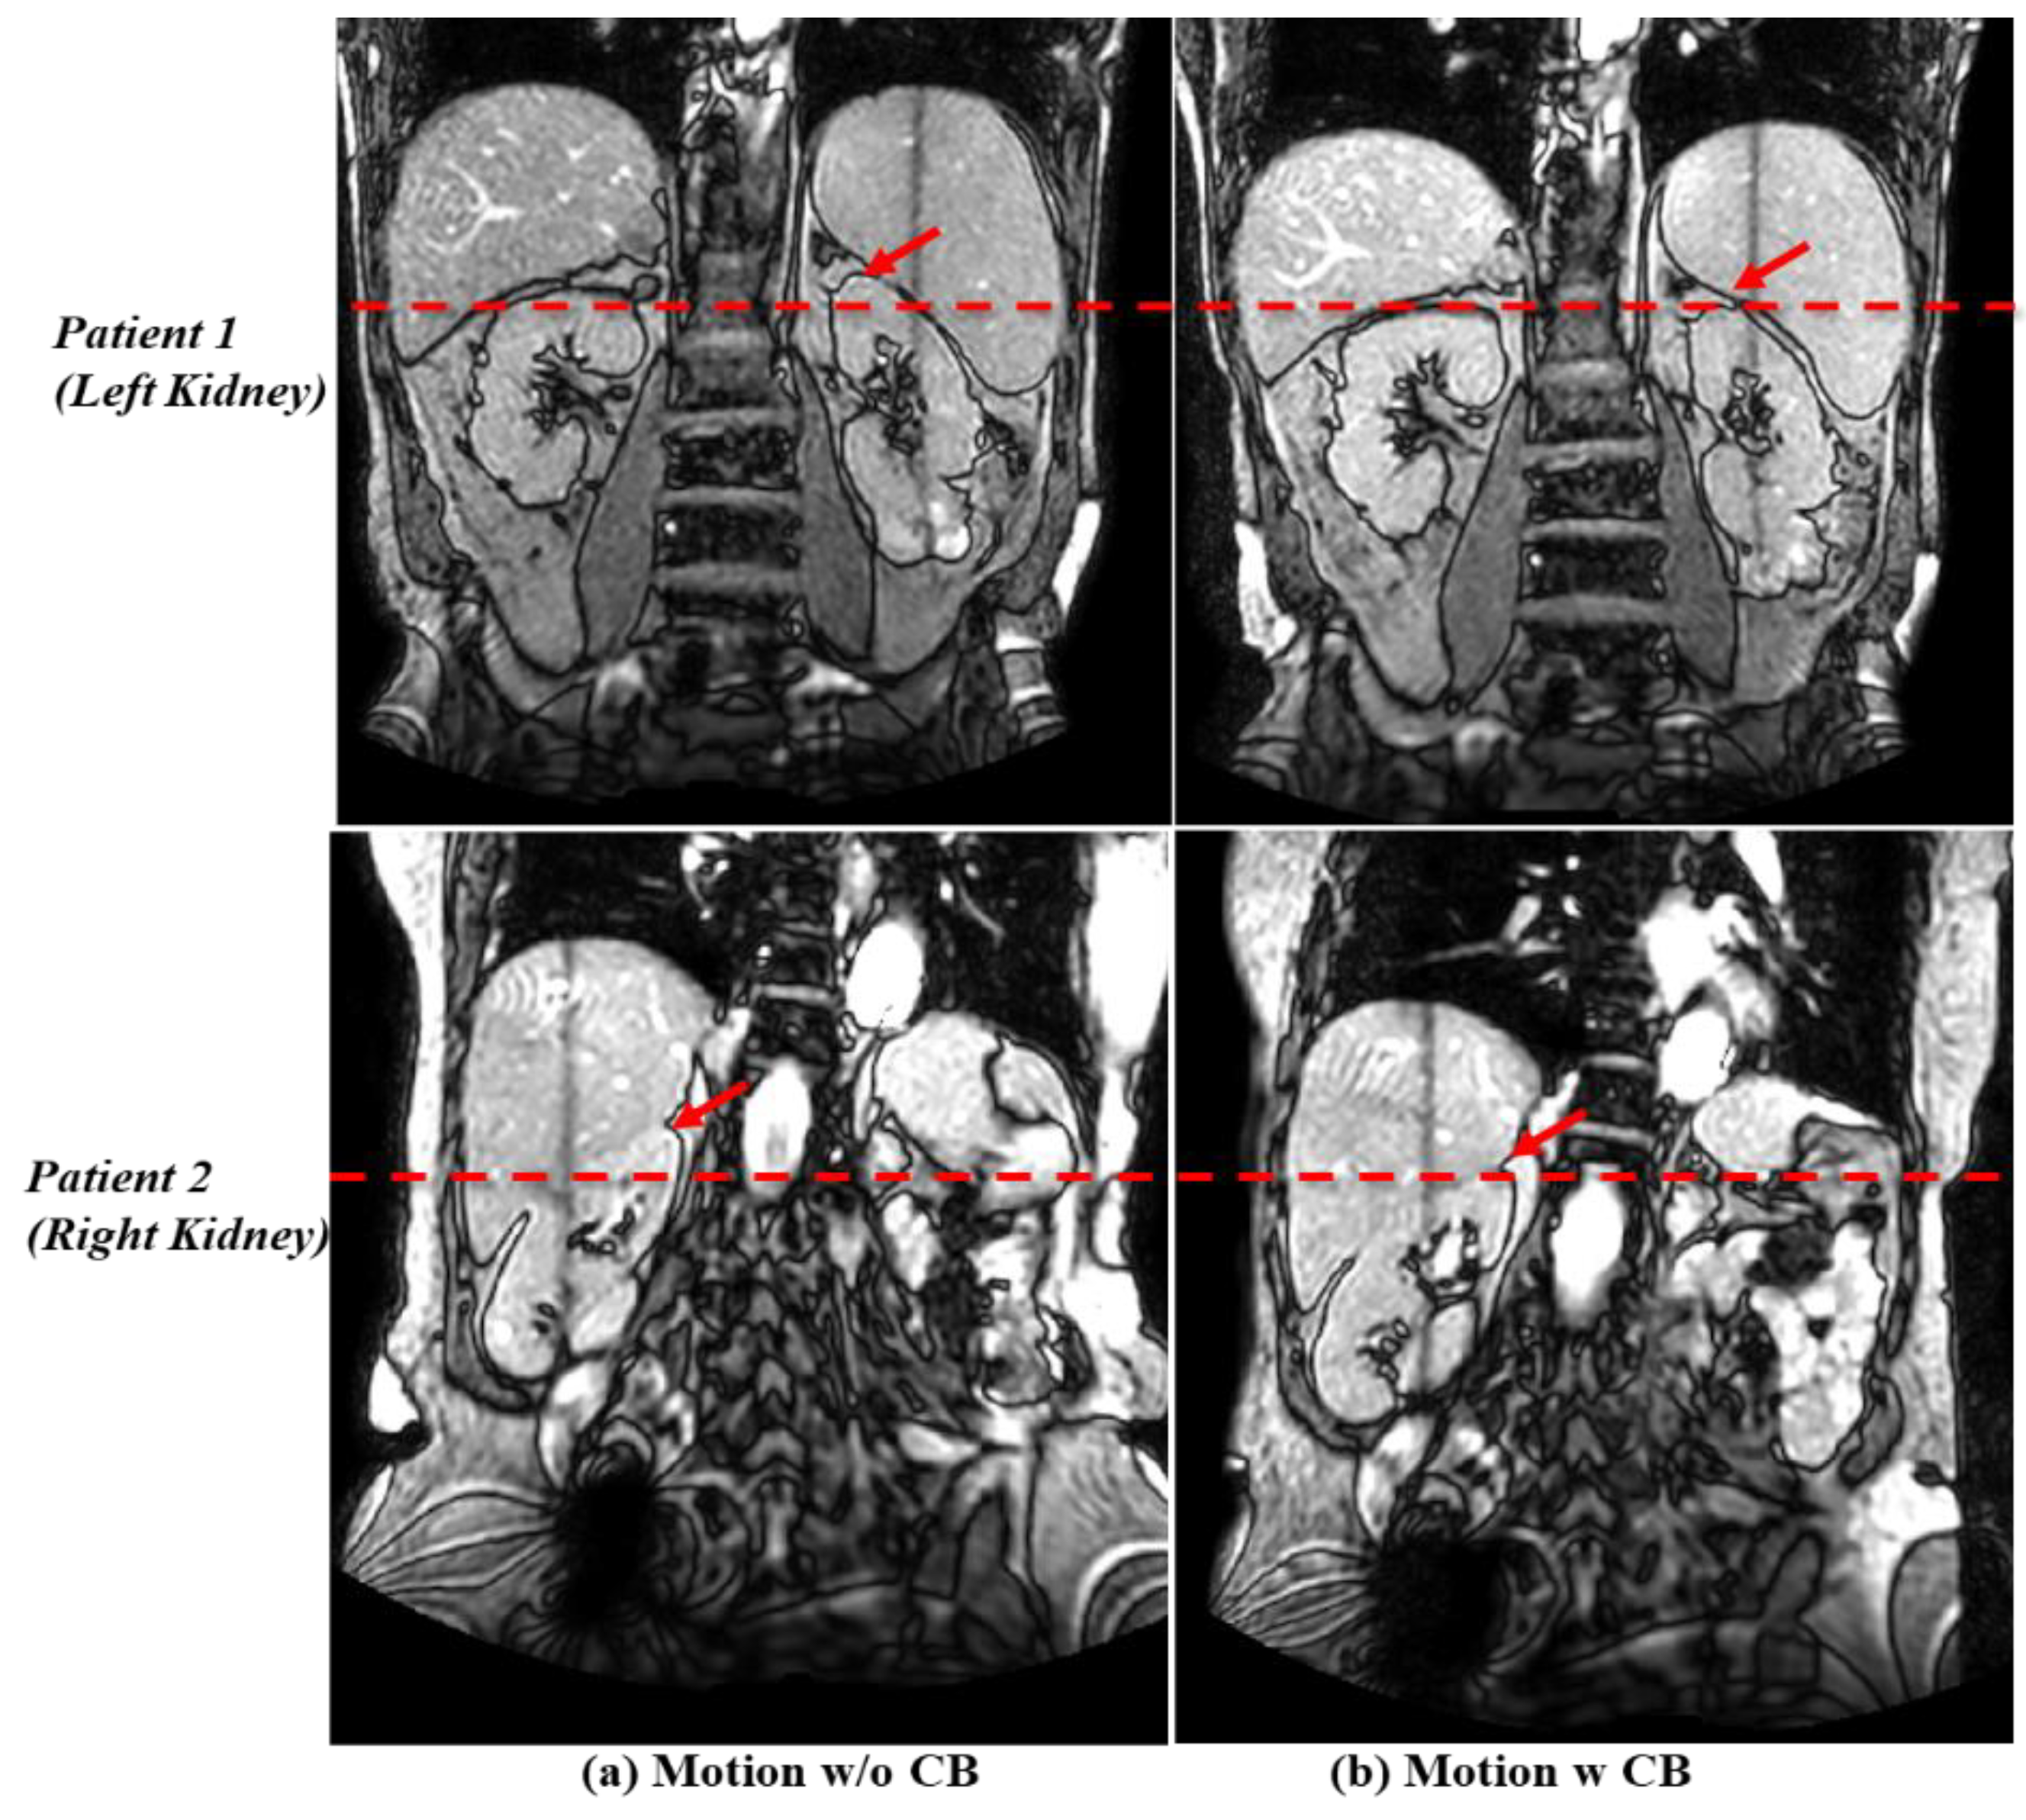

3.2. Motion Management with the Compression Belt